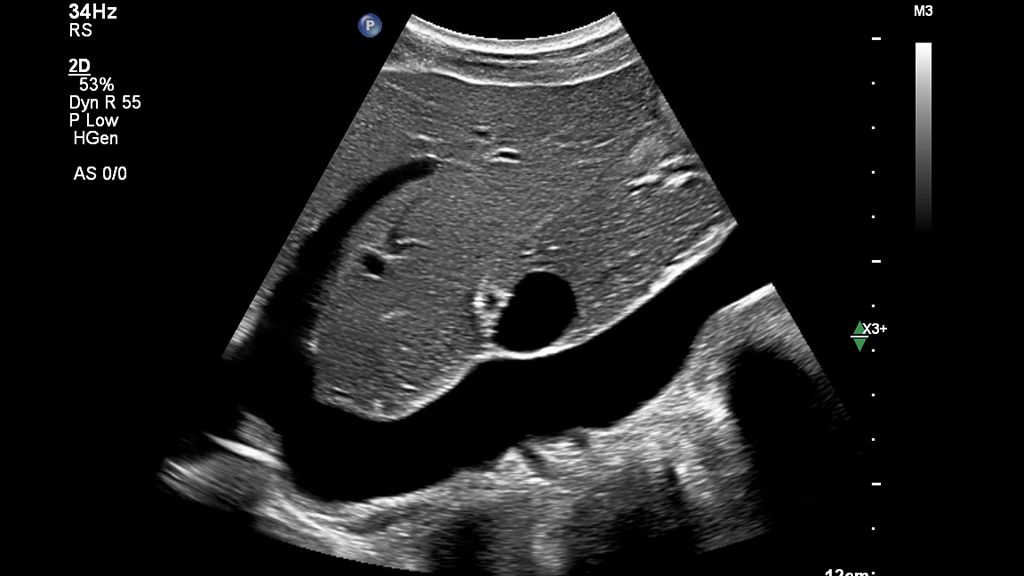

Standard workflow vs. Auto Measure Abdomen workflow

See how much time you can save with Auto Measure Abdomen in this side-by-side workflow comparison video.